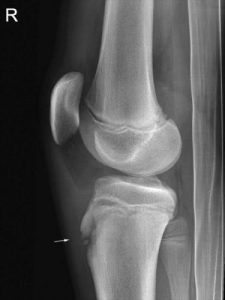

- There is a bony protrusion visible on the front of the knee below the kneecap.

When the body has a sudden growth spurt there is lots of activity as the growth plates are laying down a lot more bone cells. Then when the tendons around the knee start pulling on this bone, it causes some irritation and inflammation. This occurs right at the front of the knee at the top of the shin bone where the tendon from the thigh muscles attaches below the kneecap. It becomes inflamed and sore.